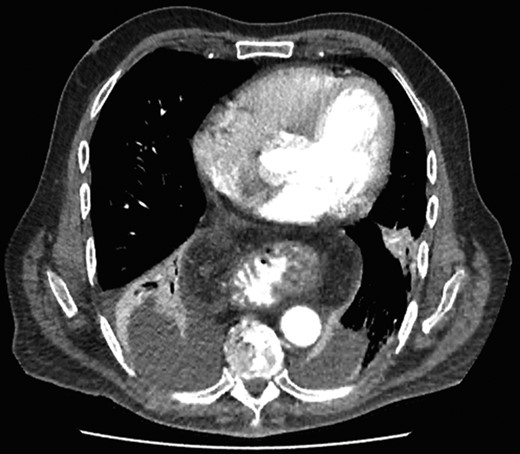

Interval gastroscopy in 2 weeks showed healing mucosal ischemia with slough from 27–30 cm (Fig. 3). Clear fluids were commenced and gradually upgraded to normal diet. Follow-up CT showed no contrast extravasation within posterior mediastinum (Fig. 4) and gastroscopy in 8 weeks showed healed esophagus.

Healing mucosal ischemia from upper, mid and distal esophagus.

CT scan at 2 weeks showing no contrast extravasation in posterior mediastinum.